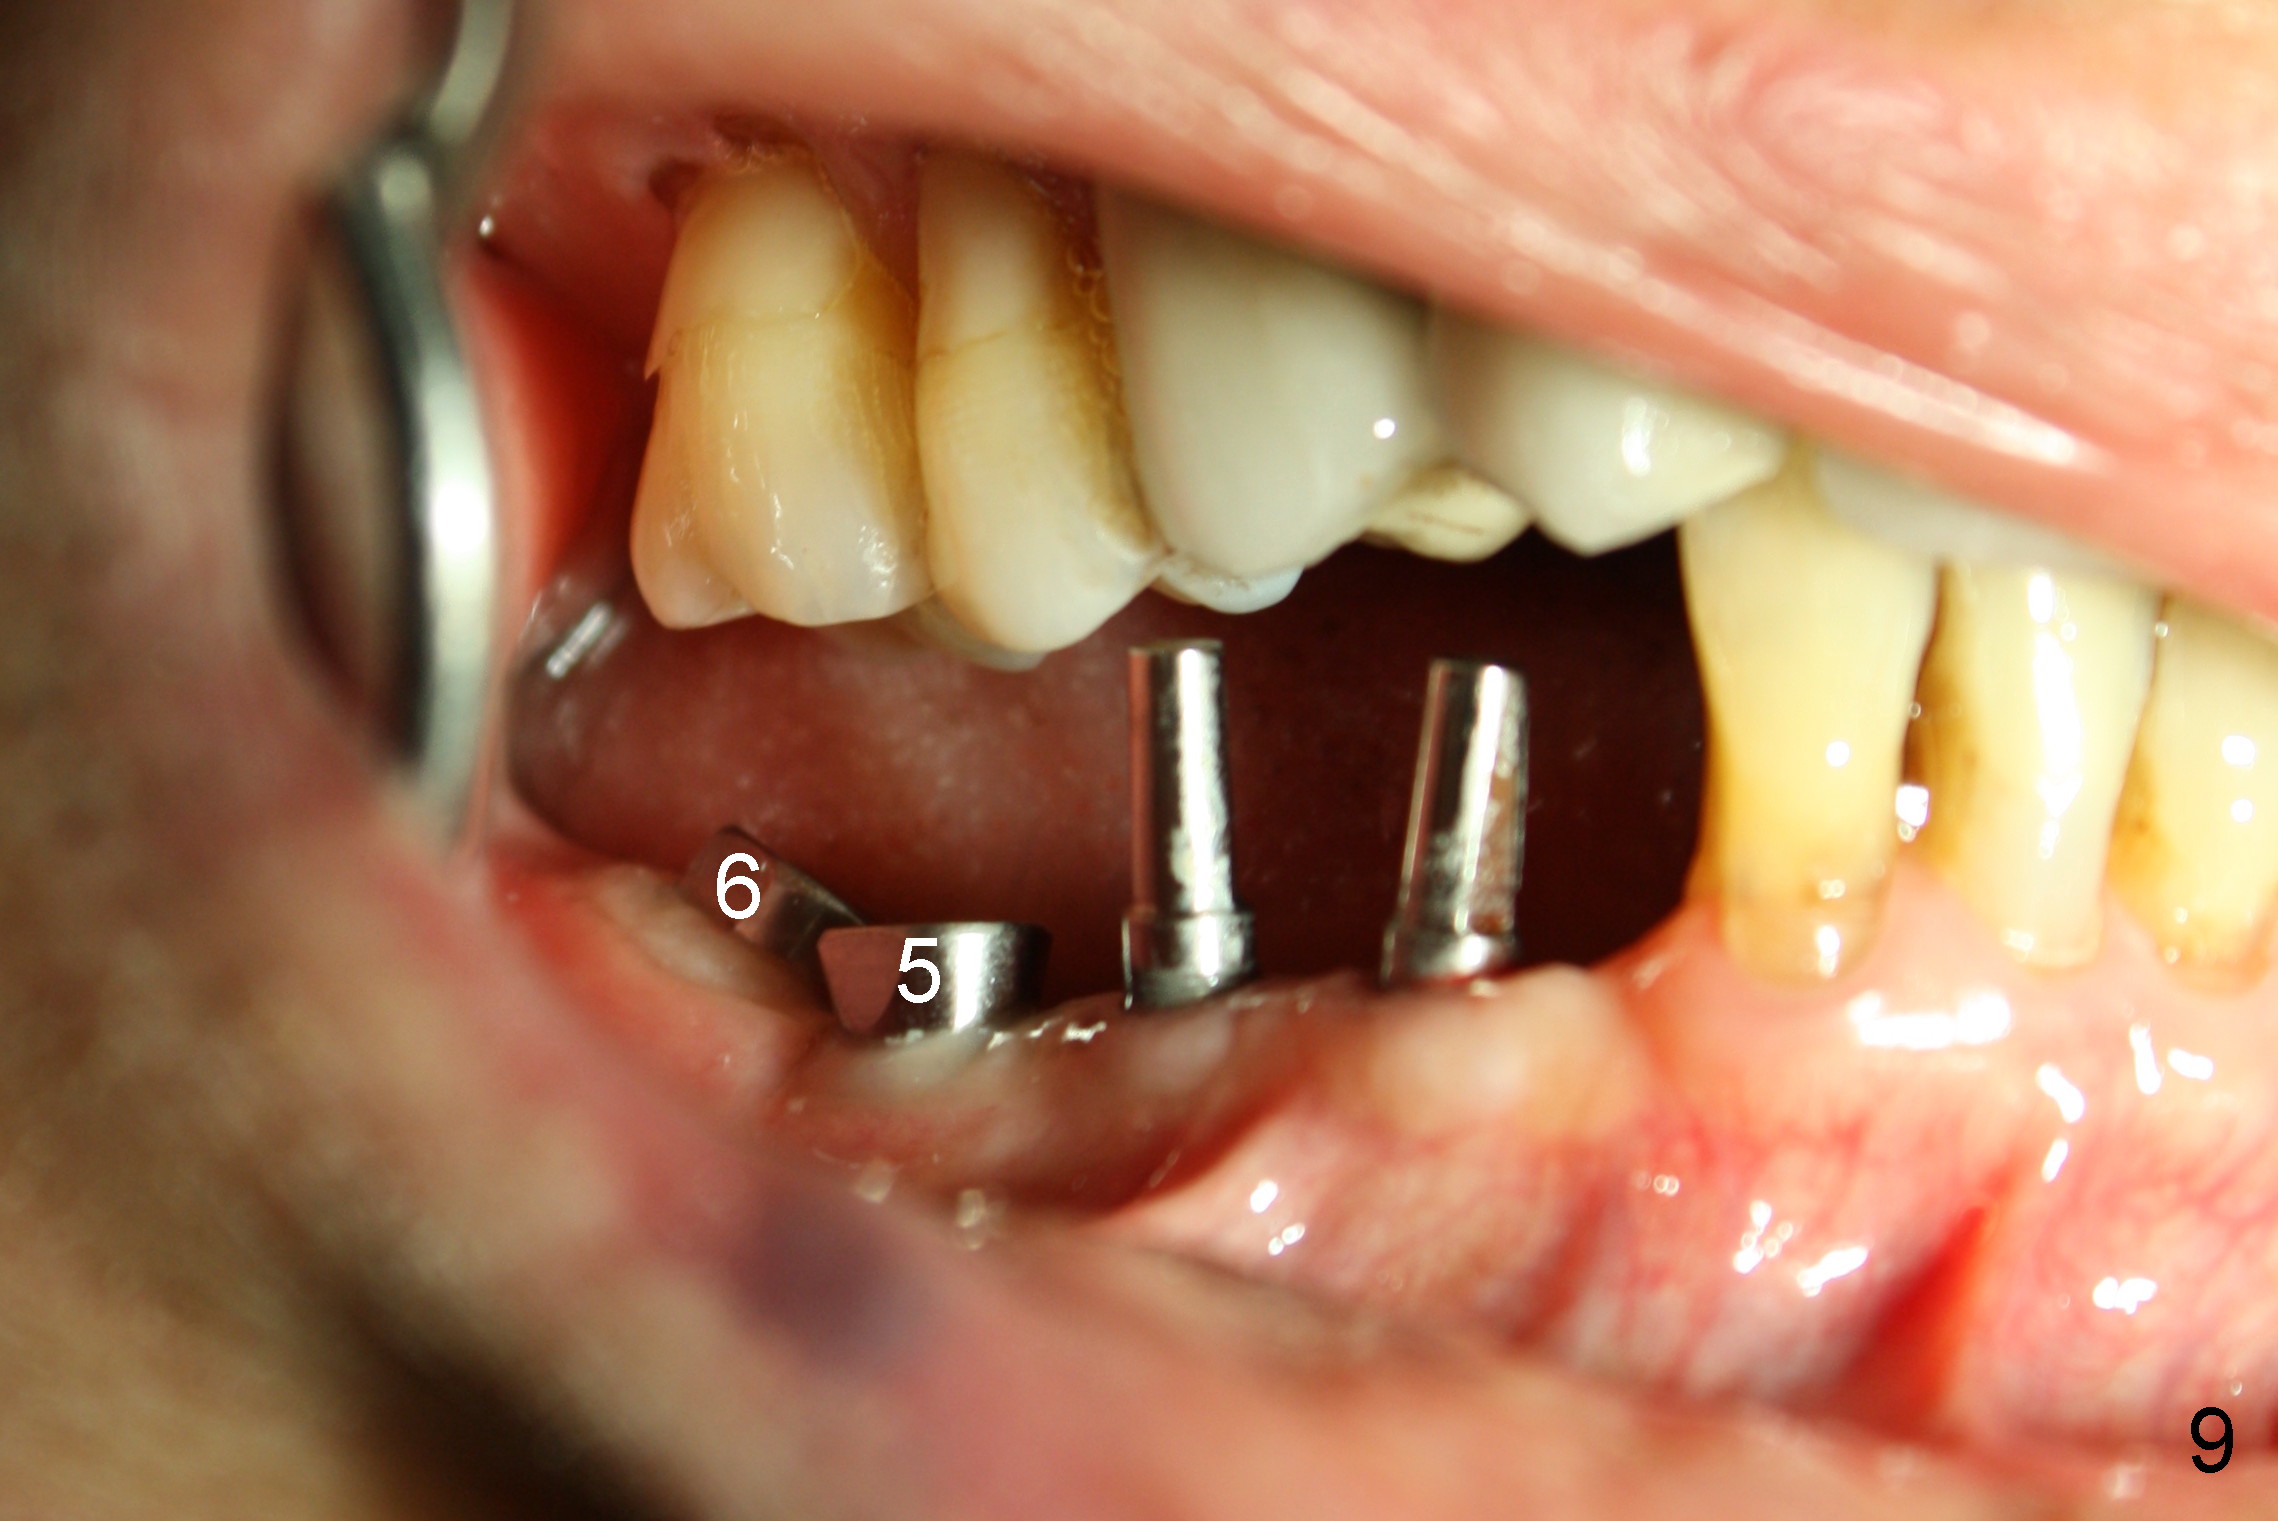

The lower right bridge (from canine (Fig.2: 3) to 1st molar (Fig.1: 6)) fails while a 77-year-old man is undergoing chemotherapy for urinary bladder cancer. The abutments of the bridge are extracted without plan for implants (Fig.4). Four months later, the patient returns for implants (Fig.3), but the ridge is narrow (Fig.5). While 2 of 3x14 mm 1-piece implant are placed at the canine and 1st bicuspid sites, 2 piece ones at the 2nd bicuspid and 1st molar sites (Fig.6: 3.5x11 mm, 5x14 mm). Soft (Fig.7-10) and hard (Fig.11) tissues heal 1 week (Fig.7) and 4 months (Fig.8-11). There is minimal bone resorption 1 year 7 months post cementation (Fig.12,13, non-splinting). It appears that narrow diameter implants are a valid solution to narrow ridge at the sites of the lower canine and premolar. As long as there are enough implants for function, the crowns are not necessary to be splinted. Surprisingly, the patient starts flossing after implant restoration. Retrospectively an immediate provisional bridge should have been fabricated.